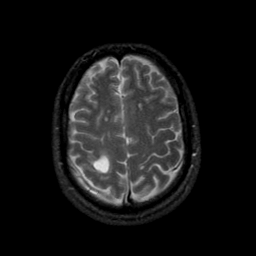

MR Study #9, April 14, 1991 -- Slice #39